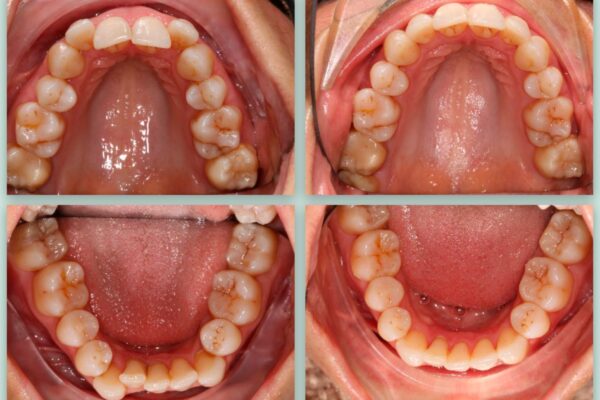

Ενδεικτικά Πριν και Μετά